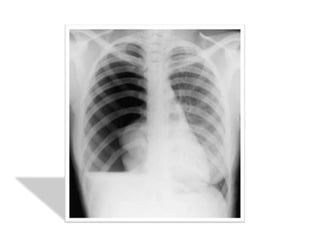

1. LA RX STANDARD DU THORAX

LA RX STANDARD DU THORAX

Résultats :

• hyperclarté avasculaire homogène périphérique

prenant tout l’hémithorax plus ou moins étendue.

• Rétraction du poumon s/f d’un moignon hyperdense

sur le hile avec distension des EIC et une netteté

anormale des côtes.

• La plèvre viscérale qui entoure ce moignon apparaît

sous forme d’un fin liséré opaque net comme tracé au

crayon

on recherchera systématiquement les signes

radiologiques associés :

• Une opacité liquidienne à niveau horizontal de la base

témoignant d’un hydropneumothorax

• Position du médiastin et du cœur éventuellement

refoulé

• Anomalies parenchymateuses homo ou contolatérales

en sachant qu’il existe une surcharge vasculaire réflexe

du coté sain

• Un aspect de petit cœur dans les formes bilatérales